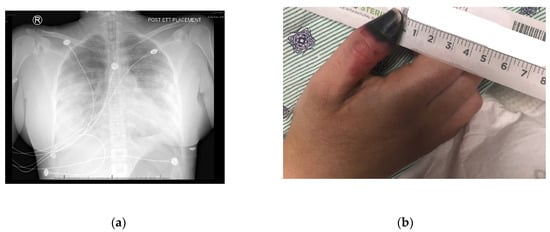

A thirty-one-year-old female (oral informed consent was obtained), with a past medical history of asthma and intermittent cocaine use, developed cough, dyspnea, hemoptysis, fever, and pleuritic chest pain several hours after receiving Bio-Alcamid gluteal injections. Despite a course of Levaquin, she required admission to her local community hospital. Initial workup at the hospital included a lower extremity doppler ultrasound, which was negative for deep vein thrombosis, and a CT without contrast that showed multiple bilateral areas of patchy infiltrates predominantly in the periphery. Occurring on day two of admission, a CT with contrast showed progressive worsening of the infiltrates, with development in the bilateral apices, and the superior and posterior left upper lobe (Figure 1a). Pulmonary artery enlargement, engorgement with redistribution of blood flow, and right-sided pleural effusion also was reported. A right-sided thoracentesis was performed.

Figure 1.

(a) Diffuse bilateral effusion- A/P view; (b) Right thumb dry gangrene.